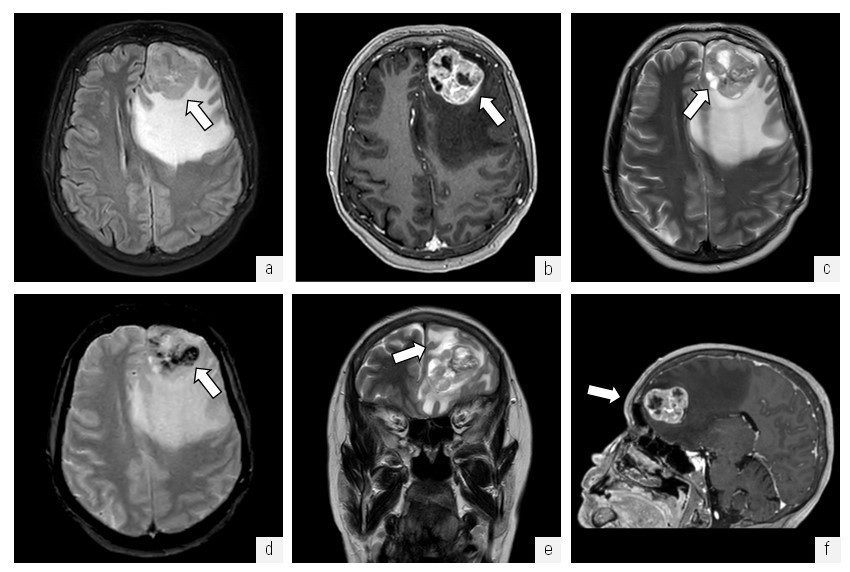

Anamnesis morbi: со слов пациентки, в мае 2019 г. заметила новообразование на коже лба, которое никак не беспокоило. В последние два года при расчесывании стала замечать образование на коже волосистой части головы, которое периодически кровоточило. В начале 2022 г. стала испытывать головную боль диффузного давящего характера, в августе 2022 г. по результатам проведения МРТ ГМ выявлено объемное образование левой лобной доли, интенсивно накапливающее контраст с наличием масс-эффекта на передние рога боковых желудочков, с зоной массивного перифокального отека (рис. 2).

Рис. 2. МРТ головного мозга. Объемное образование левой лобной области: a — МРТ в режиме FLAIR в аксиальной проекции, определяется объемное образование гетерогенно-гиперинтенсивной структуры с неровными контурами (стрелка) и выраженным перифокальным отеком, срединные структуры и боковые желудочки деформированы, смещены; б — МРТ в режиме T1 ISO с контрастным усилением в аксиальной проекции, отмечается активное неоднородное накопление контрастного препарата в структуре опухоли (стрелка); в — МРТ в режиме Т2 в аксиальной проекции, отмечаются жидкостные (некротические?) включения в структуре объемного образования (стрелка); г — МРТ в режиме Т2GRE* в аксиальной проекции, определяются включения отложений продуктов биодеградации гемосидерина в структуре объемного образования (стрелка); д — МРТ в режиме Т2 в корональной проекции, отмечается распространенная зона вазогенного отека вещества головного мозга (стрелка); е — МРТ в режиме T1 ISO с контрастным усилением в сагиттальной проекции (стрелка)

Fig. 2. MRI of the brain. Volumetric formation of the left frontal area; a — MRI in FLAIR mode in axial projection, the volumetric formation of a heterogeneous hyperintensive structure with uneven contours (arrow) and pronounced perifocal edema is determined, the median structures and lateral ventricles are deformed, displaced; б — MRI in T1 ISO mode with contrast enhancement in axial projection, there is an active heterogeneous accumulation of contrast agent in the tumor structure (arrow); в — MRI in T2 mode in axial projection, liquid (necrotic?) inclusions in the structure of volumetric education (arrow); г — MRI in the T2GRE* mode in the axial projection, inclusions of deposits of hemosiderin biodegradation products in the structure of volumetric formation are determined (arrow); д — MRI in the T2 mode in the coronal projection, there is a common area of vasogenic edema of the brain substance (arrow); е — MRI in T1 ISO mode with contrast enhancement in sagittal projection (arrow)